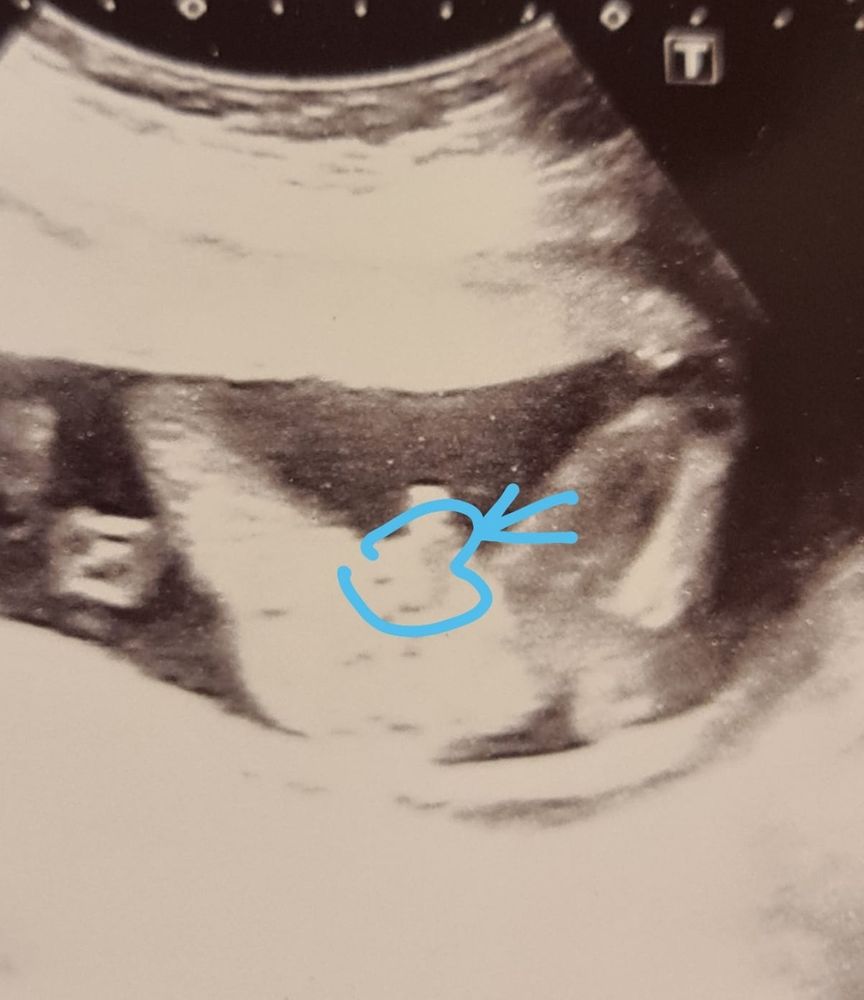

Все хорошо видно на таком сроке,вот мой с хозяйством в 17+2 Изображение